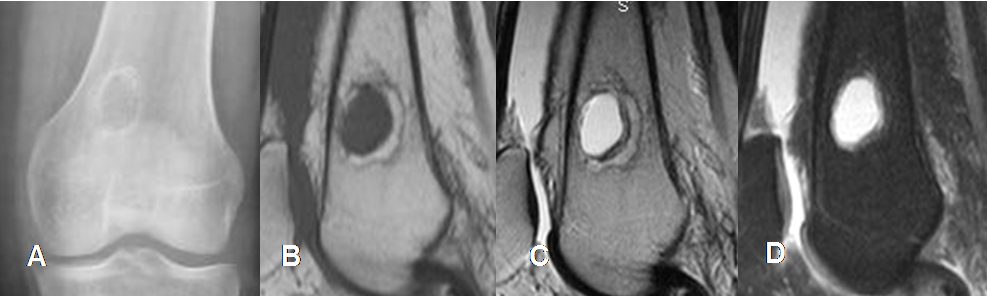

Fig 137. Quiste óseo simple.

A: Rx AP. Imagen central y diafisiaria, de bordes bien y escleróticos.

B: RM sagital en T1, C: RM sagital en T2 y D: RM sagital en STIR. La lesión sigue la señal de intensidad del agua en todas las secuencias y corresponde a quiste simple.